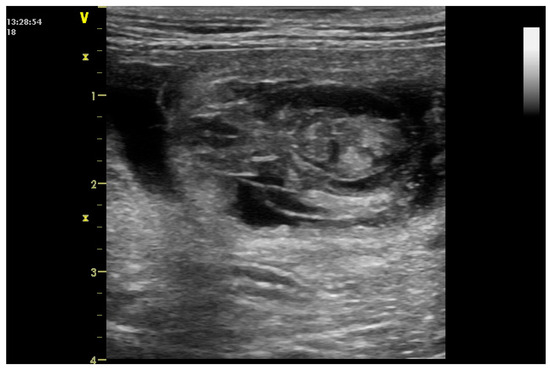

- England, G.C.W. Ultrasonographic assessment of abnormal pregnancy. Vet. Clin. N. Am. 1998, 25, 849–868. [Google Scholar] [CrossRef]

- England, G.C.W.; Russo, M. Ultrasonographic characteristics of early pregnancy failure in bitches. Theriogenology 2006, 66, 1694–1698. [Google Scholar] [CrossRef]